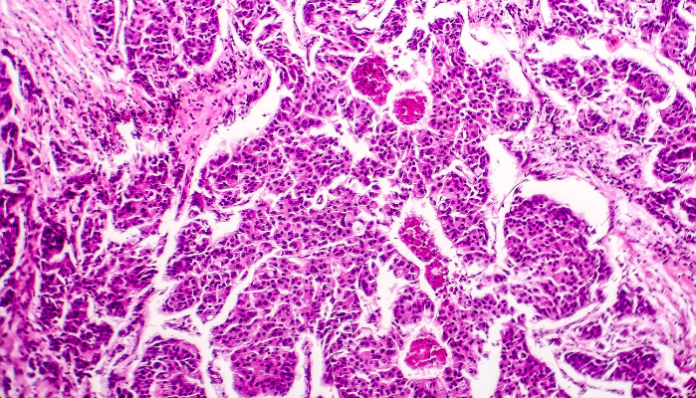

Pero el estudio de la ETH, publicado en la revista Nature y recogido por El Mundo, arroja que “las células cancerosas circulantes que posteriormente forman metástasis surgen principalmente durante la fase de sueño de los individuos afectados”. «Cuando la persona afectada está dormida, el tumor se despierta», afirma Nicola Aceto, líder del estudio y profesor de Oncología Molecular de la ETH.

En el análisis participaron 30 pacientes de cáncer y modelos de ratón. Allí, notaron que el tumor generaba más células circulantes cuando el individuo estaba dormido. También observaron que las células que abandonan el tumor por la noche se dividen más rápido; por lo tanto, presentan un mayor potencial para formar metástasis en comparación con las células circulantes que abandonan el tumor durante el día.